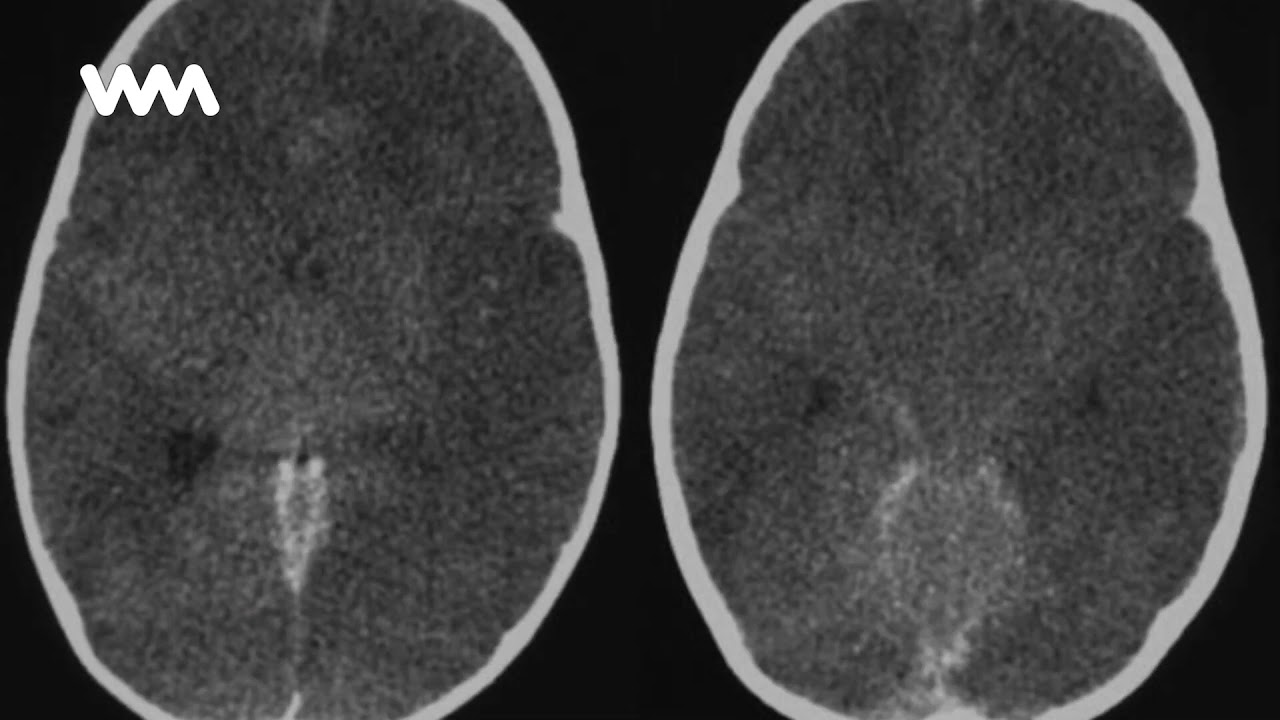

Тяжелый отек мозга